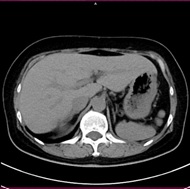

高速で230mm/秒で撮影することができ、例としておなか60cmの範囲を撮影するとした場合、約3秒の息止めで撮影することが可能です(検査の種類、目的により異なります)

高速撮影